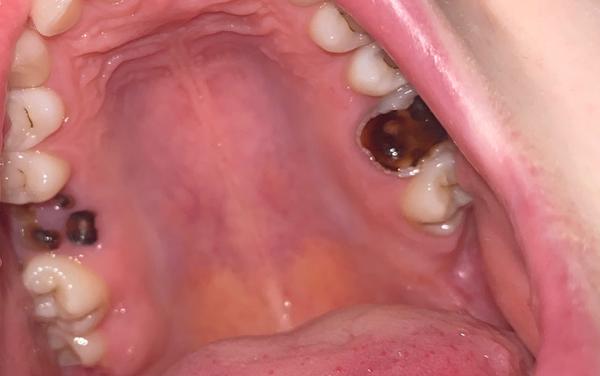

Mám hrozné zuby a bojím sa ísť k zubárovi

Zdravím, hrozné sa bojím ísť k zubárovi s takýmto stavom zubov.. ako mi to vytrhne alebo bude rezať?

Toto su mliecne zuby?